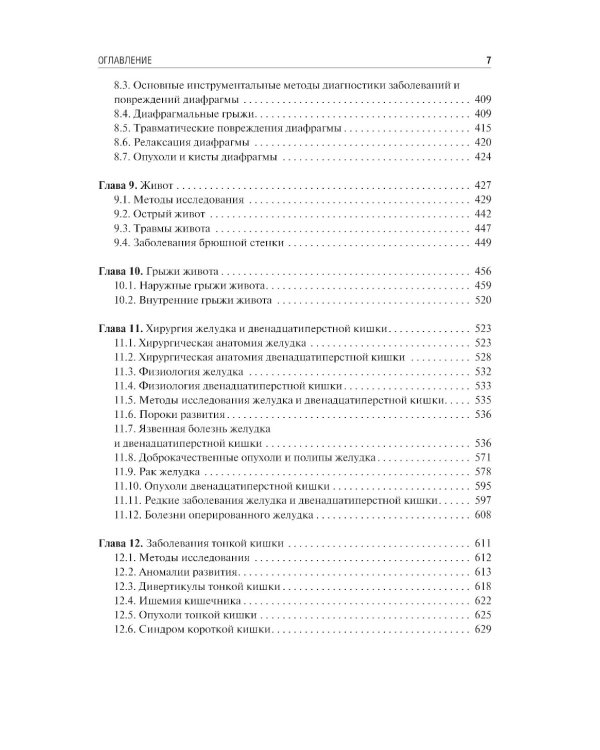

Содержание учебника соответствует программе по факультетской и госпитальной хирургии, а также квалификационной характеристике врача по специальности «Хирургические болезни» и включает главы по хирургической гастроэнтерологии, пульмонологии, кардиологии, ангиологии, флебологии и эндокринологии. В работе над ним принимали участие ведущие специалисты медицинских вузов, институтов РАН, клинических и научно-исследовательских центров. Издание предназначено для самостоятельной теоретической подготовки студентов старших курсов лечебного и педиатрического факультетов медицинских вузов, а также клинических ординаторов и аспирантов системы последипломного образования.| Издательство | ГЭОТАР-Медиа |